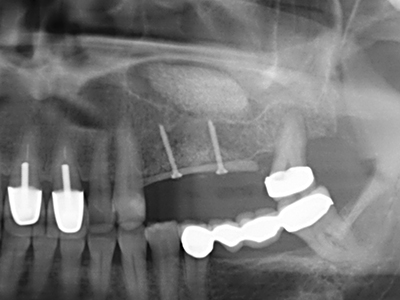

Фиг. 13: Подходяща иригация с остатъчна 4 mm дебелина на костта е важна за този 52-годишен пациент по време на разделянето на костта.

Фиг. 14: Поставяне на RSX имапланта (Bego Implant Systems, Bremen).

Фиг. 15: Прегледът на рентгеновата снимка след 1 година показва стабилно състояние на нивото на костта.

Фиг. 16: Интраоралните условия също са стабилни с поставените импланти в кератизираната гингива.